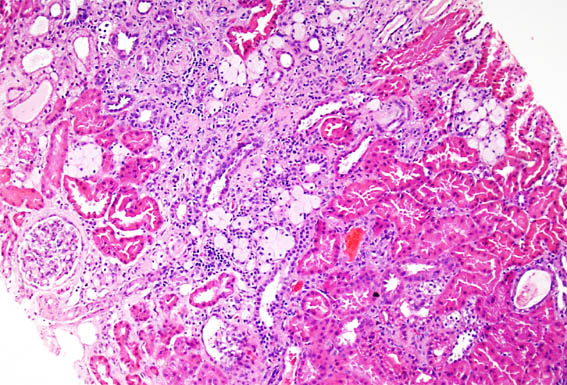

Figura 1. H&E, X100.